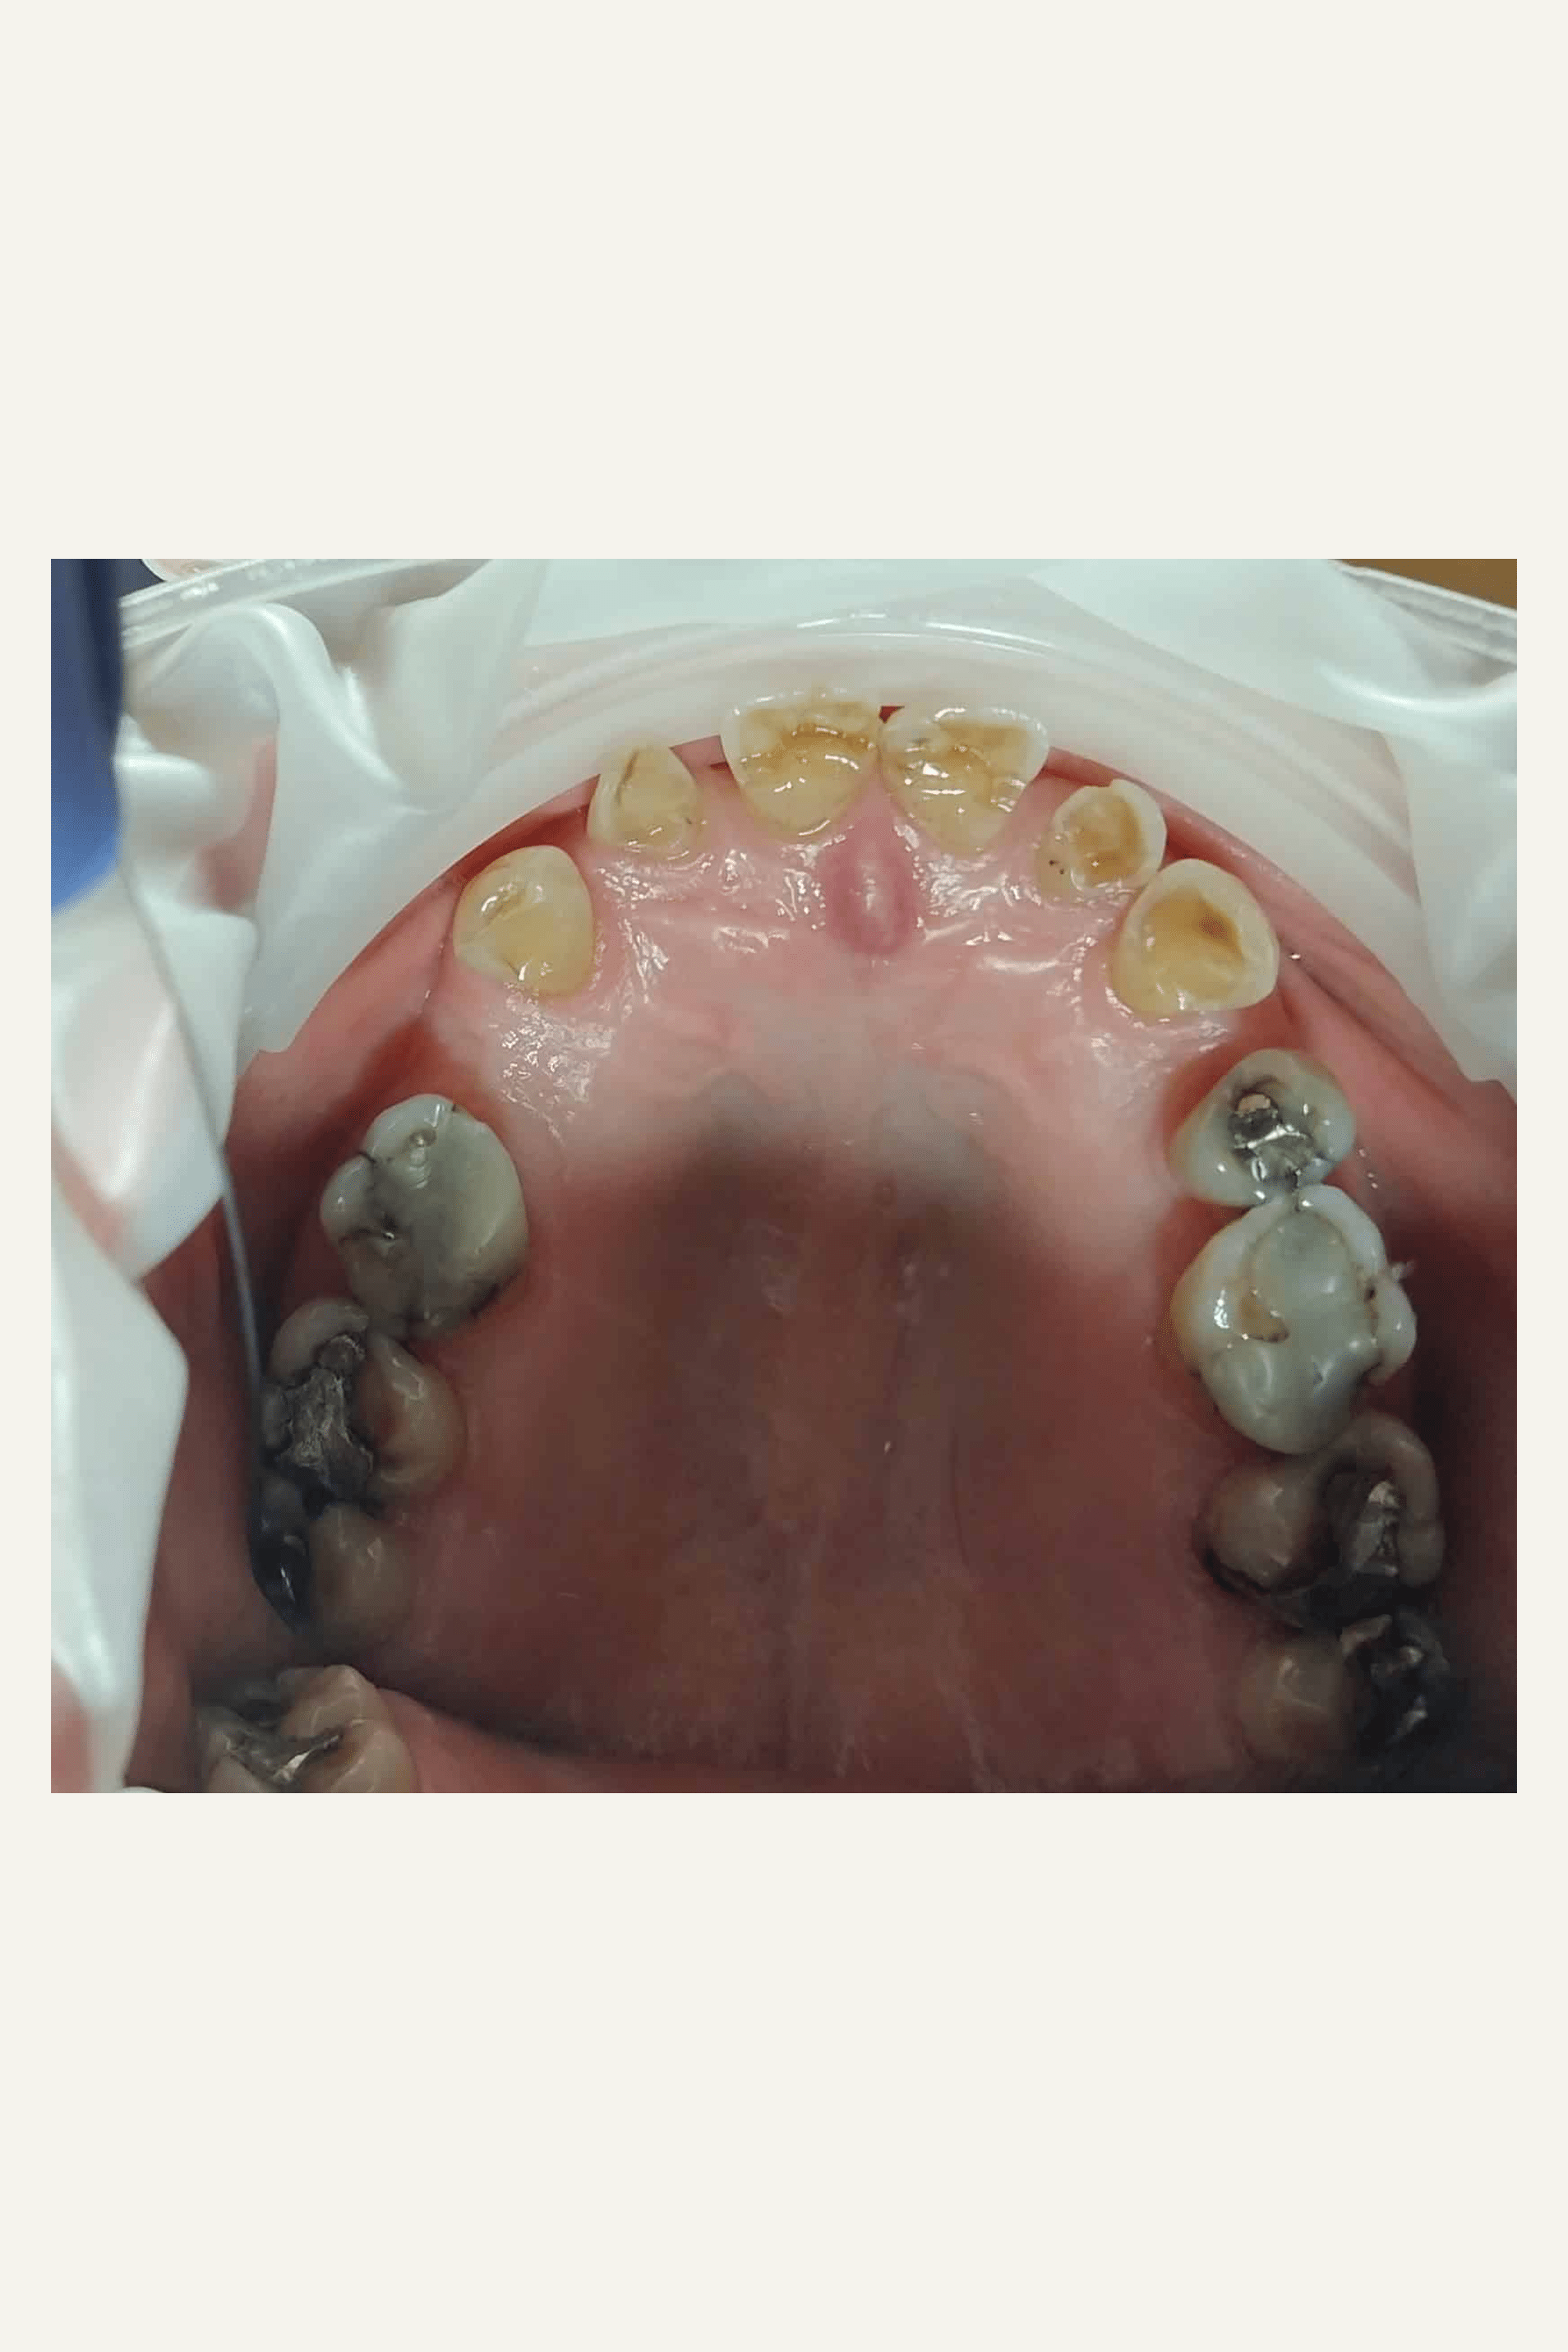

Her ses et eksempel på slid i overkæbe og underkæbe.

På billedet ses desuden infraktioner (små revner i tænderne) i relation til gamle amalgam fyldninger. Amalgam kan med tiden udvide sig og forårsage revner i tænderne, som i værste tilfælde kan resultere i, at tænderne knækker. Infraktioner er som regel symptomfri, men ikke desto mindre anbefales det at skifte amalgam fyldninger før man får tandpine. Hvis uheldet er ude, så kan en tand der ikke har fået skiftet sin amalgam fyldning i tide knække, så tanden skal rodbehandles eller endnu værre knækker tanden så meget at tanden ikke kan reddes og skal fjernes.

Mange amalgam fyldninger kan uden problemer ligge i tænderne i 15-20 år, men så begynder det at blive aktuelt at skifte fyldningerne. Tandlægen vil anbefale skift af fyldninger, når der begynder at komme en mørk misfarvning omkring amalgam fyldningen eller hvis der er tydelige infraktioner i tanden.

De fleste gamle amalgam fyldninger kan skiftes med en simpel plastfyldning, hvis den skiftes i tide.